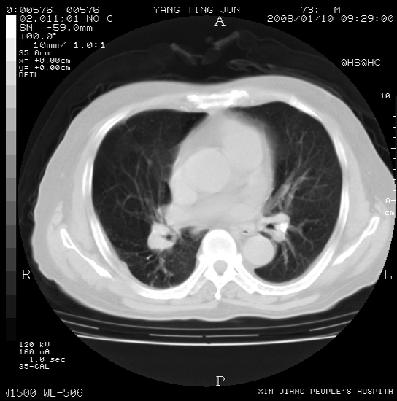

标题: CT11288:M70Y,右肺小结节影

男性,70y,咳嗽伴胸闷15日余。曾有肺tb病史。

右肺中叶内侧段周围型肺癌可能性大.双侧陈旧性肺结核伴右肺部分间质纤维化\\右肺上叶后段感染,右侧胸膜肥厚粘连.

2.右肺上叶见一不规则软组织密度影,边缘有毛刺及棘状突起,胸膜牵拉,并见一增粗僵硬的供血血管.周围型肺癌的可能性大.

2右肺中叶小结节灶,有毛刺及胸膜凹陷征,近肺门侧供血血管粗硬、僵直,考虑周围型肺癌  。